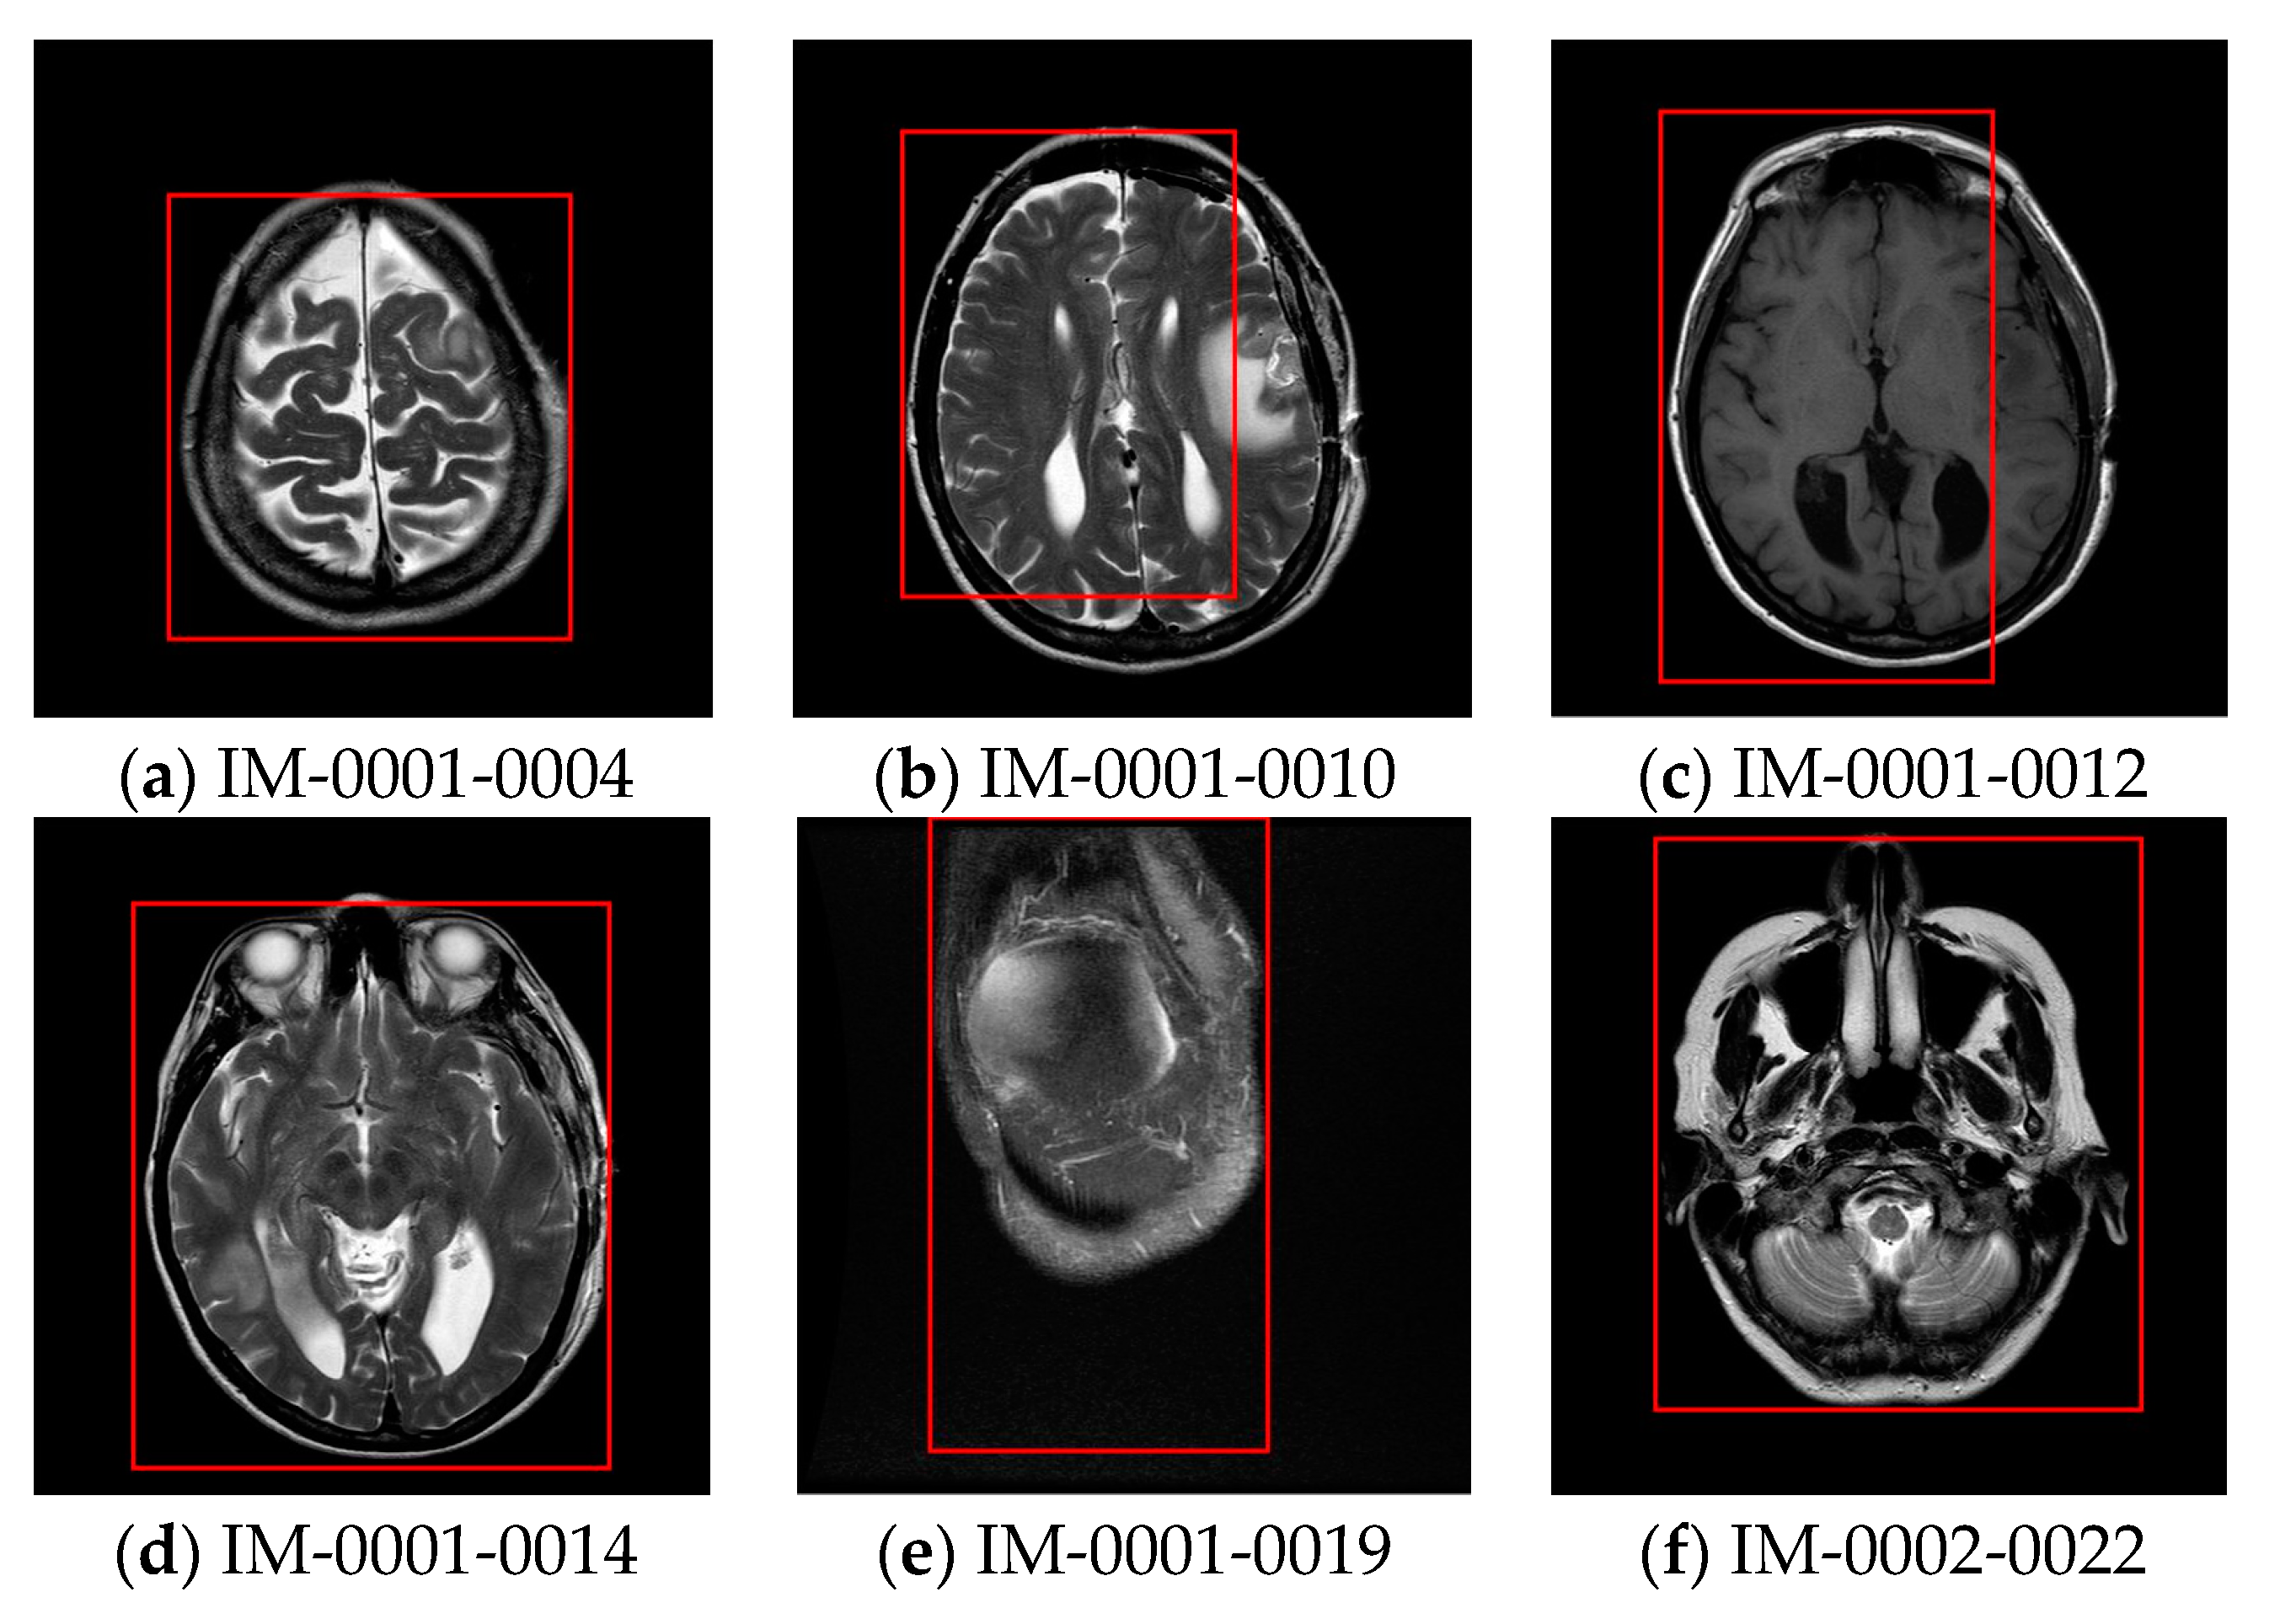

| Images for test | Coordinate of upper left of ROI | Coordinate of lower right of ROI |

|---|---|---|

| IM-0001-0004 | (102,118) | (405,453) |

| IM-0001-0010 | (83,70) | (434, 469) |

| IM-0001-0012 | (83,55) | (434,486) |

| IM-0001-0014 | (75,66) | (426,481) |

| IM-0001-0019 | (102,1) | (357,480) |

| IM-0002-0022 | (81,17) | (448,448) |